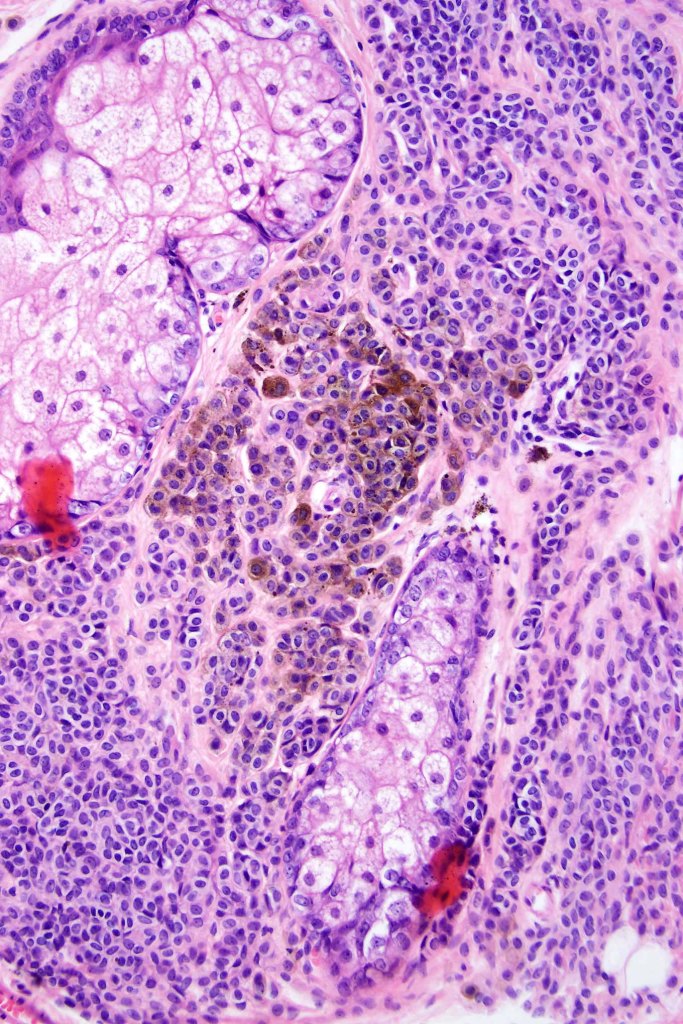

This is uncommon and presents clinically with a history of recent change in color of a common or less often congenital nevus causing concern for melanoma by the clinician. Some, but not all are probably deep penetrating and combined nevus variants. Others may represent follicular type-A cell nests. It is characterized by the presence of deep nest(s) of type -A nevus cells surrounded by & with overlying type-B nevus cells.